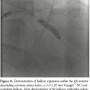

Case Report. A 75-year-old man with a history of hypertension presented to the emergency department on day 1 with inferior wall ST-elevation myocardial infarction (STEMI). He denied any prior cardiac history. He was taken directly to the cardiac catheterization lab for primary PCI. Angiogram revealed acute thrombosis within the right coronary artery (RCA), with 100% occlusion. PCI was performed within the infarct vessel, with placement of two bare-metal stents and reduction of the lesion to 0% residual stenosis and TIMI 3 flow in the distal vessel (Figures 1A and 1B).